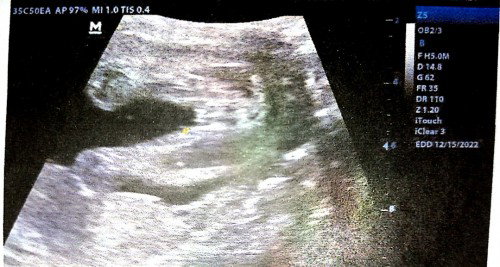

parang girl po .eto naman po un sakin😁

Girl po, eto rin yung sakin 🥰